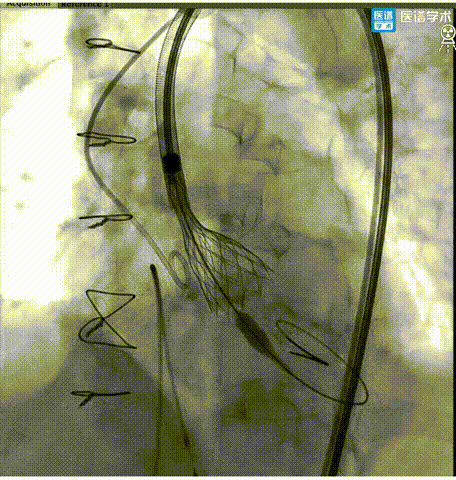

8. 第三次释放后,超声、造影评估示瓣膜植入深度、工作形态良好、微量瓣周漏,交换猪尾导管测的平均跨瓣压差2mmHg,手术圆满成功。